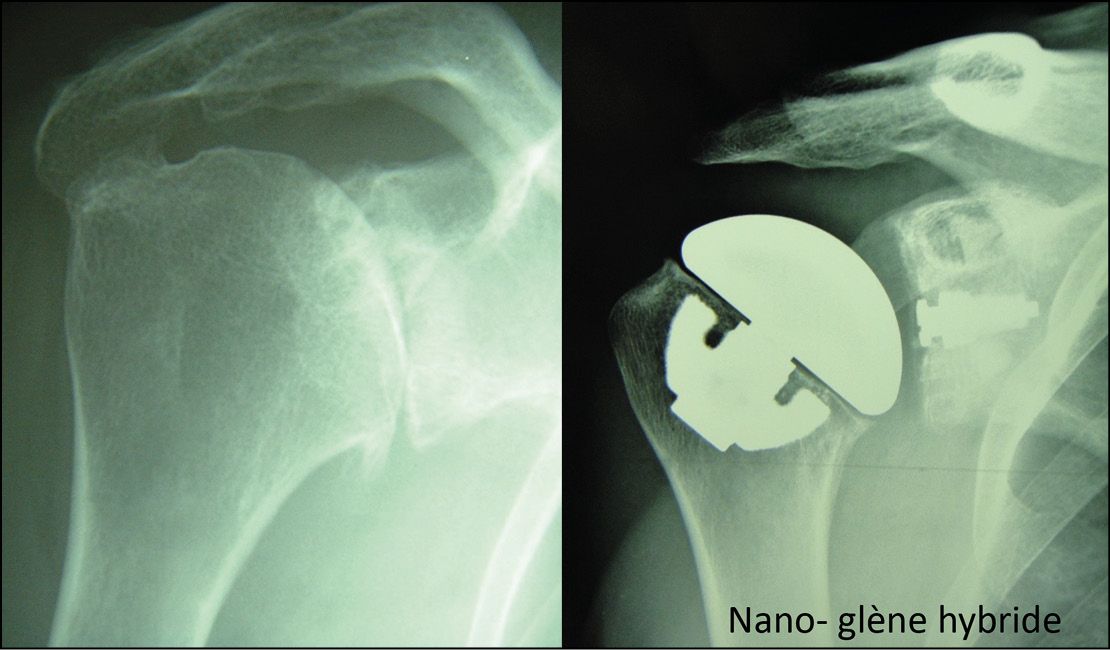

Concentric osteoarthritis in a young subject is the perfect indication for stemless TSAa because there will be good-quality bone stock and a future revision will be made easier by the use of a stemless design. Longer survival can also be achieved by using a hybrid glenoid component to avoid the need for cement (Fig. 12).